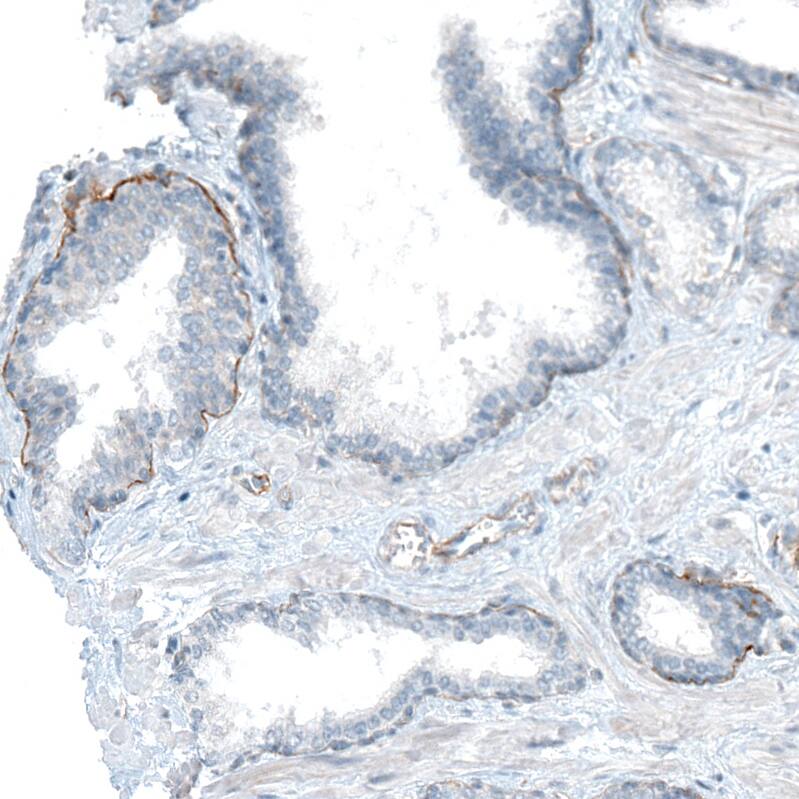

Staining of human placenta shows strong basement membrane positivity in trophoblastic cells.